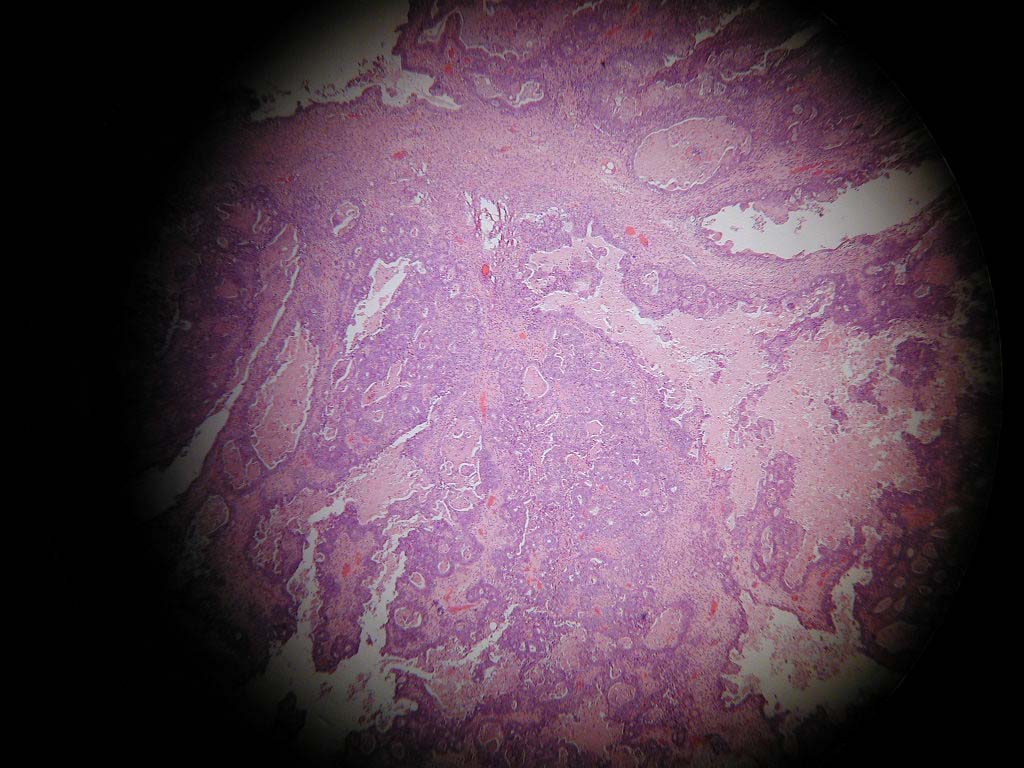

Below are 2 photomicrographs comparing different ways to attach a Nikon Coolpix 990 to a microscope.  The first picture is taken at 4x with in descending order a Nikon Coolpix 990 with a Leitz 10X eyepiece screwed into the lens mount for the Coolpix which was then inserted into the phototube of the  Olympus BH2 microscope.  The second picture also at 4X and from the same case shows  the Coolpix 990 attached connected by a an Optem relay lens connected by 2 "connecting pieces" which sit on top of an Olympus C mount which in turn sits on top of an Olympus BX51 microscope [Optem relay lens 257014 (screws into lens mount of camera), Optem connecting piece 257015, Optem connecting piece 29-90-56, Olympus C mount UDA-4E00435].  Both microscopes have "plan" lenses.  I think you will agree that the Optem setup has the image better centred on the CCD chip.  This allows more flexibility with field of view so you don't always have to be so far zoomed in to remove vignetting (the circular image).  There is also  is more uniform light intensity and more "plan" like focusing across the image.

Coolpix, Optem setup and Olympus BX51